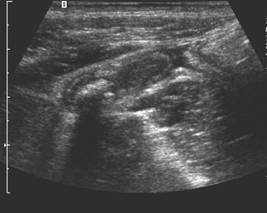

Compresia gradata sonografica este sugestiva pentru stabilirea cu acuratete a diagnsticului de apendicita. Apendicele apare ca o terminatie oarba, un fragment intestinal neperistaltic, cu originea la nivelul cecului. Printr-o compresiune maximala, se masoara diametrul antero-posterior al apendicelui. Testul este considerat pozitiv daca diametrul antero - posterior al apendicelui necomprimat este de 6 mm sau mai mult. Prezenta unui apendicolit stabileste diagnosticul. Imaginea ecografica a unui apendice normal, care este o structura tubulalara inchisa la un capat, usor compresibila, cu un diametru de 5 mm sau mai putin, exclude diagnosticul de apendicita acuta. Studiul este considerat negativ daca apendicele nu se vizualizeaza si nu exista o masa tumorala sau fluid pericecal. Cand se exclude ecografic diagnosticul de apendicita acuta, o scurta evaluare a restului cavitatii abdominale ar fi de preferat pentru stabilirea unui alt diagnostic. La femeile active sexual, organele pelvine genitale ar trebui vizualizate atat transabdominal, cat si transvaginal, pentru a exclude o patologie ginecologica care ar putea cauza durerea abdominala acuta.

Diagnosticul ecografic al apendicitei acute are o sensibilitate de 78 - 96 % si o specificitate de 85 - 98 %. Ecografia poate fi realizata in scop diagnostic la copii si femeile insarcinate, desi aplicabilitatea ei este oarecum limitata in ultimele luni de sarcina.

Ecografia are o serie de limite nete si rezultatele sunt dependente de experienta celui care o efectueaza. O imagine fals pozitiva poate sa apara in prezenta unui proces inflamator periapendicular determinat de inflamatia tesuturilor limitrofe; o dilatare a trompelor uterine poate fi confundata cu o inflamatie apendiculara, resturi de fecale neevacuate pot mima un apendicolit, iar la pacientii obezi, apendicele poate fi incompresibil atat datorita procesului inflamator acut, dar si datorita stratului de tesut adipos. Ecografii fals negative pot sa apara in conditiile unei limitari a procesului inflamator la varful apendicelui, in apendici cu localizare retrocecala, atunci cand este marit si poate fi confundat cu intestinul subtire sau in caz de perforatie apendiculara cand este comprimat.

Fig . 9 Apendicita acuta cu prezenta unui stercolit in lumenul apendicular